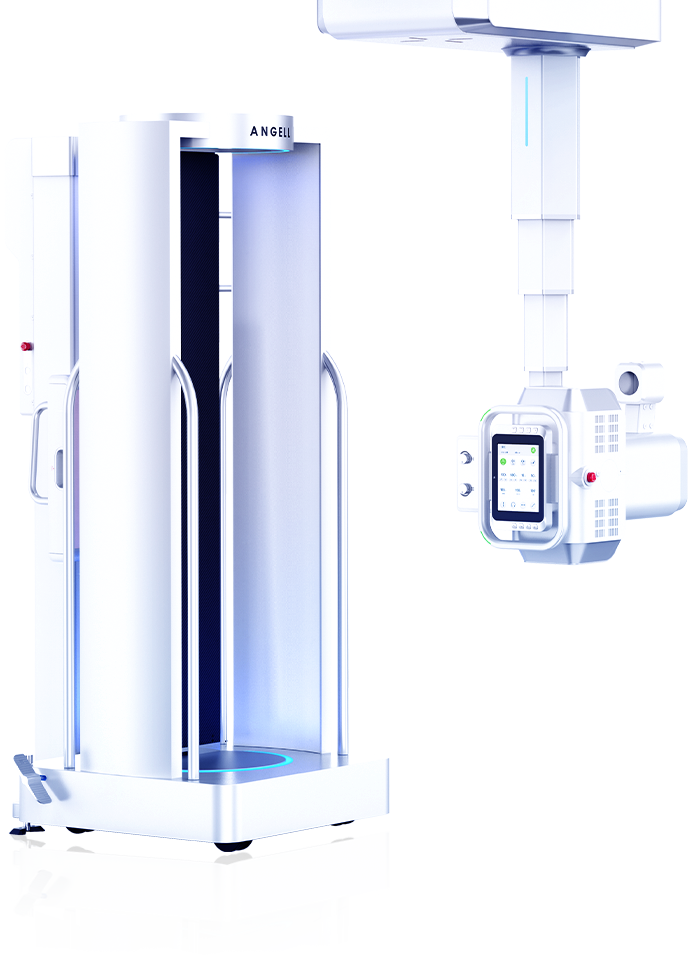

最大350mm FOV

可移動式站臺設(shè)計

可移動站臺

2D+3D一站式快速檢查

FOV最大350mm

支持雙腿或雙側(cè)髖關(guān)節(jié)掃描 | 方便對比,降低漏診誤診